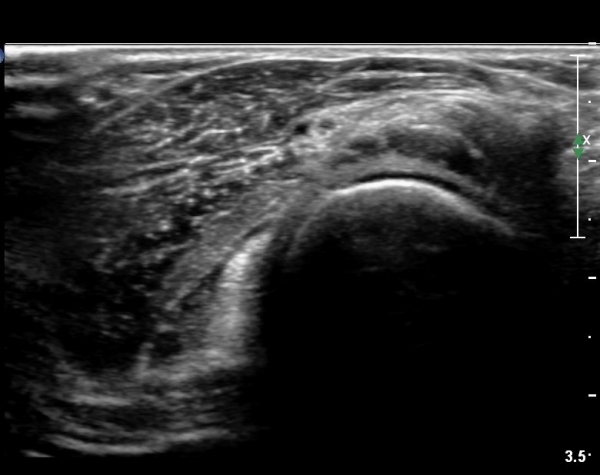

ŽÃÊÀÚ¸¦¸»´ÜÀ¸·Î  À̵¿ÇÏ´Ï ¿ä°ñ¸ñ ºÎÀ§¿¡¼­ Ä¿´Ù¶õ ³¶Á¾ÀÌ Èİñ°£ ½Å°æÀ» ¾Ð¹ÚÇÏ´Â °ÍÀÌ

°üÂûµÈ´Ù(»çÁø 4, 5)

Á¶±Ý´õ ŽÃËÀÚ¸¦ ¸»´ÜÀ¸·Î À̵¿ÇÏ´Ï ³¶Á¾Àº ÀÛ¾ÆÁö°í ȸ¿Ü±Ù »çÀÌ¿¡ À§Ä¡ÇÏ´Â Èİñ°£ ½Å°æÀÇ

ºÎÁ¾ÀÌ °üÂûµÈ´Ù(»çÁø 6)

Èİñ°£ ½Å°æ Á¾´Ü¸é°Ë»ç¿¡¼­ ³¶Á¾¿¡ ÀÇÇÑ Èİñ°£ ½Å°æ ¾Ð¹Ú°ú  Èİñ°£ ½Å°æÀÇ ºÎÁ¾ÀÌ °üÂûµÈ´Ù(»çÁø 7).